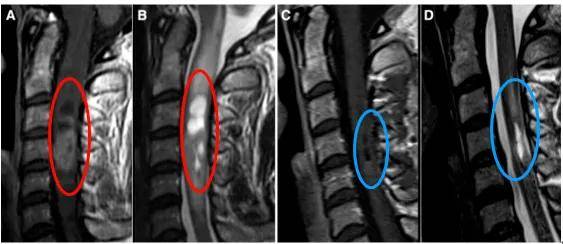

怀着希望,礼小姐前往德国,数日后接受Krauss教授主刀的手术。在常规体感诱发电位监测下,教授采用后方入路,在确保无任何神经损伤的前提下成功全切肿瘤。

手术效果显著,术后12天复查证实肿瘤完全切除,术后水肿基本消失,术前颈椎疼痛症状逐渐缓解。术后两周礼小姐顺利出院,一个月后快速恢复并重返正常生活。

术前严重的神经症状往往预示不良预后,术前症状持续时间越长,术后神经系统恢复越差。Krauss教授证实了神经状态与预后的相关性:术前McCormick 1级患者未恶化为4级,而术前McCormick分级较高的患者术后恶化几率较高,改善为较低分级的几率降低。这种效应在髓内室管膜瘤患者中尤为明显,且肿瘤次全切除术后复发可能性高于完全切除术。